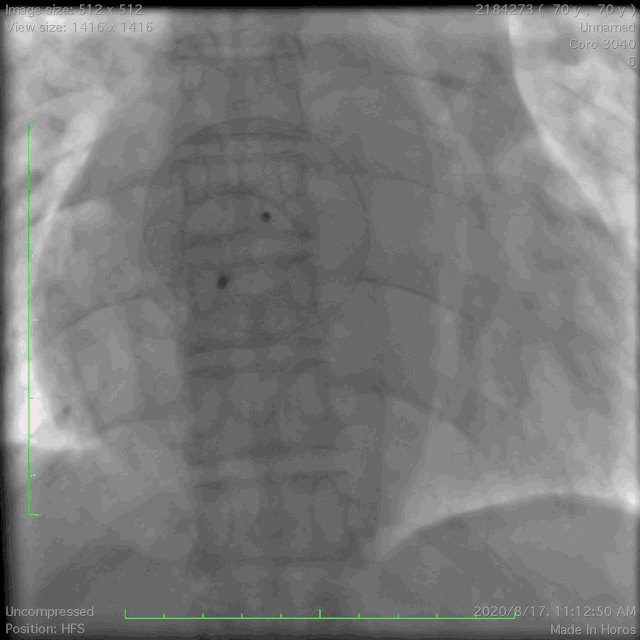

● 主动脉根部解剖

cta分析